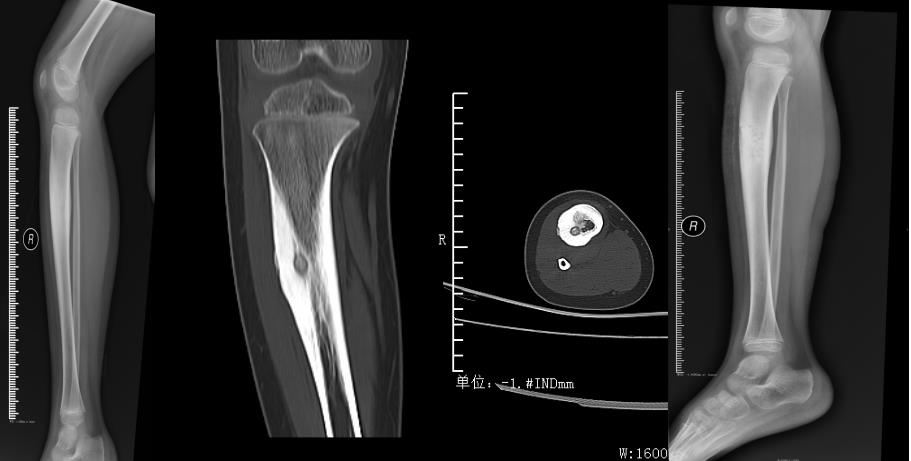

玉林市中西医结合骨科医院——骨病骨肿瘤股骨头坏死专科,是全国股骨头坏死保髋联盟成员单位,玉林市中医重点专科建设单位,是广西区内较早成立的、专注于股骨头坏死、骨病与骨肿瘤的特色科室。科室深耕上述疾病领域多年,始终恪守“精准诊疗、微创为先、中西结合”的理念,吸引了大量区内外患者慕名求医,每年开展的髋关节置换手术超千台,以精湛技术为众多患者重塑行走希望。

科室配备有专业的DAA关节置换工具、微创保髋工具、针对早期股骨头坏死的专业冲击波一体机、可用于清除骨肿瘤的超高转速磨钻等专业仪器,为病人治疗提供了强有力的硬件支持。